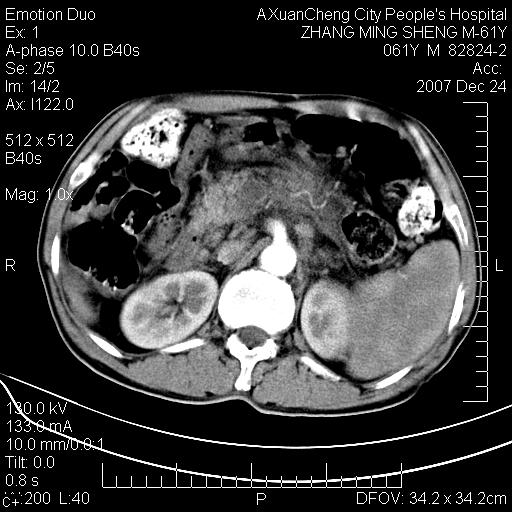

标题: CT11031:M61Y,胰腺占位

大家侃侃门静脉和胆管系统怎么回事,肝内转移?

胰腺癌肝转移

肝硬化,门脉高压,脾肿大;弥漫性肝癌,肝内、门脉、腹膜后淋巴结转移,肝内外胆管扩张,胰头区占位,建议mr检查

胰腺癌伴肝内转移;门脉、肠系膜上v癌栓形成。

考虑为:胰腺癌伴肝脏转移、腹膜后淋巴结转移,门静脉及肠系膜上静脉瘤栓形成。

胰体尾癌伴肝内转移,门静脉及肠系膜上静脉瘤栓形成.